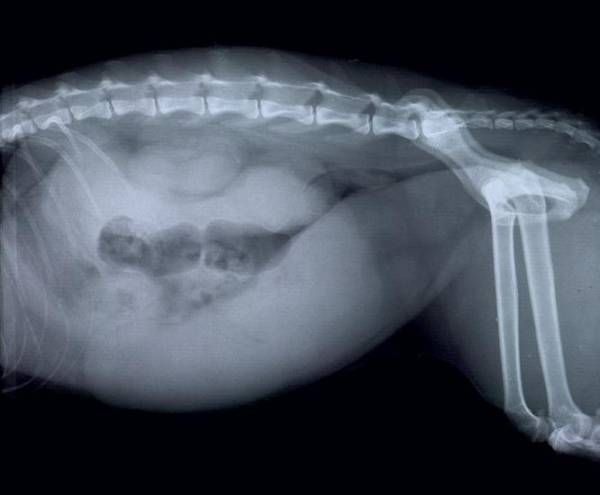

Дивлячись на фото важко повірити, що крихітна матка здатна розтягнутися до таких розмірів! Часом за добу утворюється більше двох літрів гною!

Однак ознаки піометри іноді непомітні аж до розриву матки. Особливо якщо собака літня, гладка і малоактивна (спить собі і спить, вона майже завжди спить). Гній поступово накопичується всередині, а потім виливається в очеревину. Розливний перитоніт вбиває за лічені години! Необхідна термінова операція, інакше загибель неминуча. Такий розвиток подій можливий при закритій формі недуги, коли весь гній або його більша частина залишається всередині матки. У сук поджарой конституції можна помітити деяке збільшення живота (іноді недосвідчені власники думають, що дівчинка завагітніла або переїла). Живіт може збільшуватися поступово, протягом декількох тижнів, або різко – за кілька днів (залежить від швидкості накопичення гною).